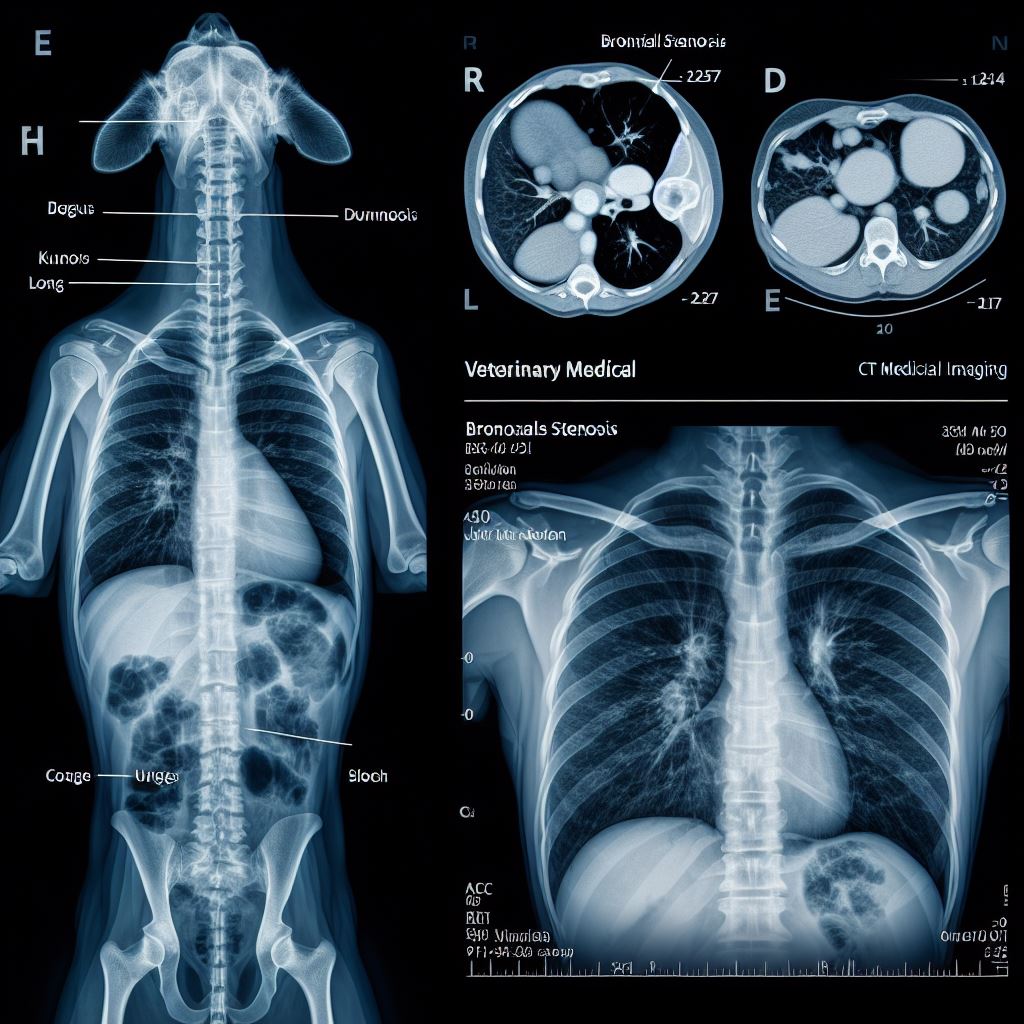

강아지 기관지 협착증 원인과 증상, 치료 방법 알아보기 사진